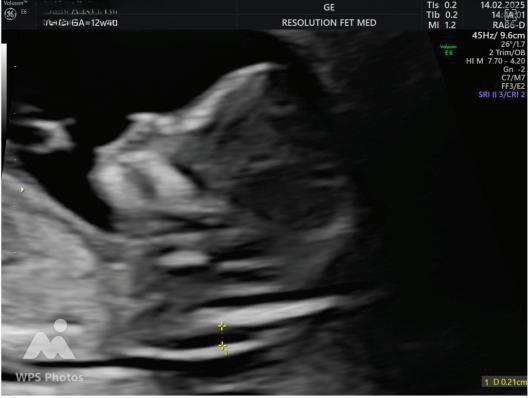

NASAL BONE:

Hypoplasia defined as length <2.5mm.

Absent METHOD OF MEASUREMENT

• Mid saggital plane.

• Good face profile.

• At 45 degree angle with imaginary line from forehead to chin.

• 3 echogenic lines.

• Absent nasal bone is more common if The gestation is 11 than 13 weeks. The fetal nuchal translucency is high. The mother is Black.